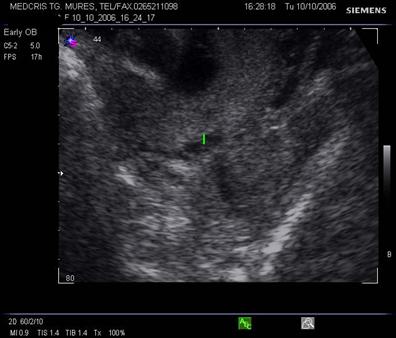

Fig. nr.217. Placenta praevia centrala la 15 saptamani ( linia indica raportul placenta praevia cu orificiul cervical intern)